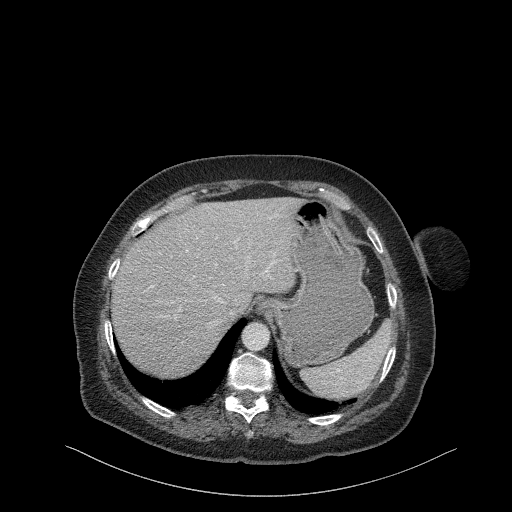

Reconstructed NATIVE CT scan (cycle consistency)

Full window (WL 1023.5, WW 4095 β†’ Low βˆ’1024, High +3071)